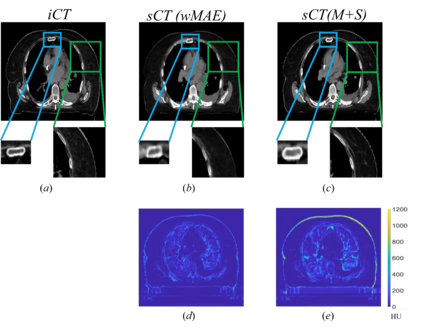

Purpose: In some proton therapy facilities, patient alignment relies on two 2D orthogonal kV images, taken at fixed, oblique angles, as no 3D on-the-bed imaging is available. The visibility of the tumor in kV images is limited since the patient's 3D anatomy is projected onto a 2D plane, especially when the tumor is behind high-density structures such as bones. This can lead to large patient setup errors. A solution is to reconstruct the 3D CT image from the kV images obtained at the treatment isocenter in the treatment position. Methods: An asymmetric autoencoder-like network built with vision-transformer blocks was developed. The data was collected from 1 head and neck patient: 2 orthogonal kV images (1024x1024 voxels), 1 3D CT with padding (512x512x512) acquired from the in-room CT-on-rails before kVs were taken and 2 digitally-reconstructed-radiograph (DRR) images (512x512) based on the CT. We resampled kV images every 8 voxels and DRR and CT every 4 voxels, thus formed a dataset consisting of 262,144 samples, in which the images have a dimension of 128 for each direction. In training, both kV and DRR images were utilized, and the encoder was encouraged to learn the jointed feature map from both kV and DRR images. In testing, only independent kV images were used. The full-size synthetic CT (sCT) was achieved by concatenating the sCTs generated by the model according to their spatial information. The image quality of the synthetic CT (sCT) was evaluated using mean absolute error (MAE) and per-voxel-absolute-CT-number-difference volume histogram (CDVH). Results: The model achieved a speed of 2.1s and a MAE of <40HU. The CDVH showed that <5% of the voxels had a per-voxel-absolute-CT-number-difference larger than 185 HU. Conclusion: A patient-specific vision-transformer-based network was developed and shown to be accurate and efficient to reconstruct 3D CT images from kV images.